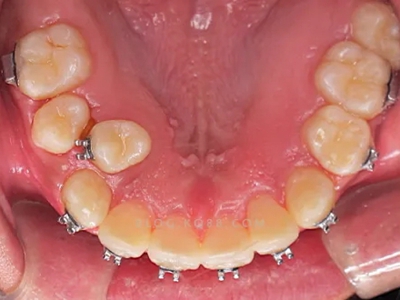

对于阻生牙的处置需要首先明确阻生牙齿发育情况是否正常,对于由于早期外伤或其他原因造成发育异常,如牙根弯曲、短根等情况的阻生牙,还应根据患者的综合情况,决定牙齿是否保留。

发育正常的牙齿同时正畸治疗又不需要进行拔牙矫治,通常需要对阻生牙进行牵引治疗,引导进入牙弓,而对于发育异常的阻生牙加之正畸治疗需要进行拔牙矫治,通常可以考虑将阻生牙拔除,而避免再拔发育正常的前磨牙,即降低了正畸治疗的难度及不确定性,又保留了相对正常的牙齿。